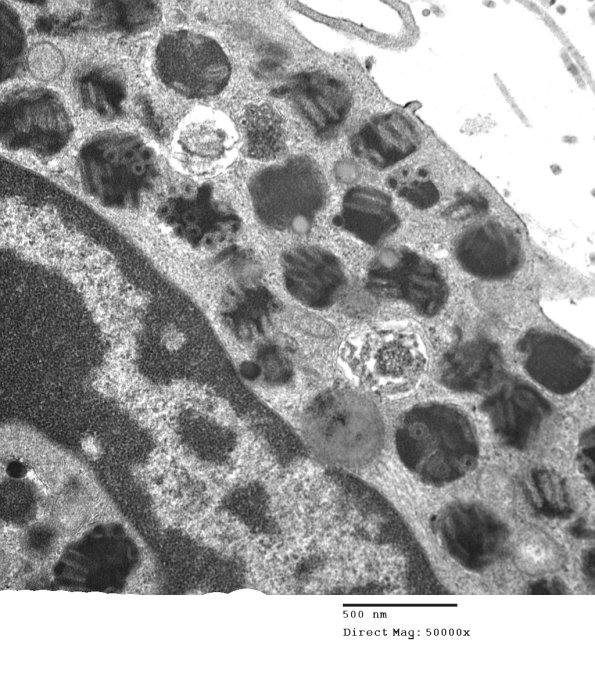

A mast cell and its subcellular granule ultrastructure is shown at various magnifications.